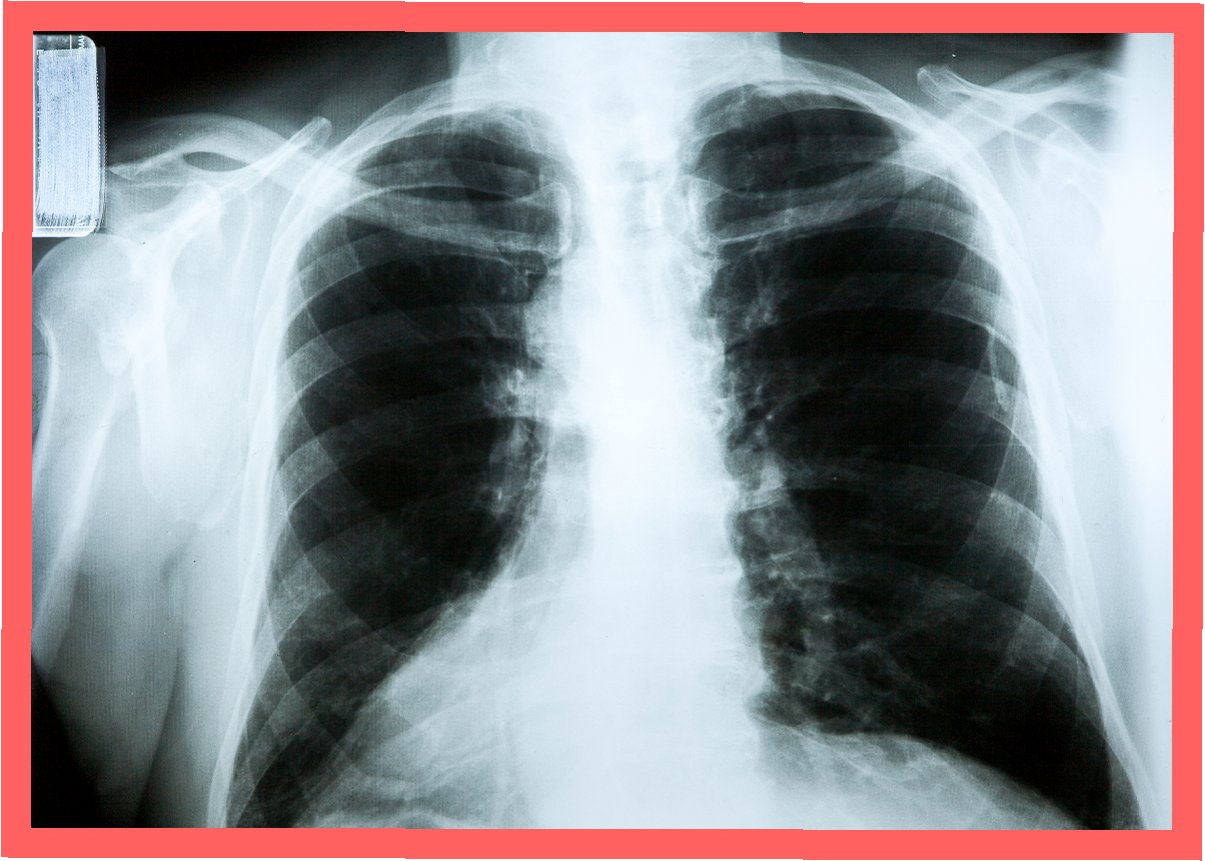

사고 발생 5년 뒤인 2019년부터 밤마다 원인 불명의 고열에 시달리던 사이먼스 씨는 병원을 찾았습니다. CT 검사 결과, 사고 당시 흡입했던 먼지 파편이 폐 깊숙이 들어가 배출되지 못하고 딱딱하게 굳어 왼쪽 폐 기관지를 완전히 막고 있다는 충격적인 사실이 밝혀졌습니다. 그는 '기계에 깔려 움직일 수 없을 때 먼지를 들이마셨는데, 그게 깊이 들어가 굳어버렸다'고 당시를 설명했습니다.

의료진은 이물질이 기관지에 박히면서 신체가 칼슘으로 둘러싸 격리하는 과정에서 석회화가 진행된 것으로 판단했습니다. 정밀 검사 결과, 좌측 폐는 5년간의 감염으로 기능을 완전히 상실한 상태였습니다. 의료진은 처음에는 석회화된 부분만 제거하려 했으나, 손상 범위가 너무 넓어 결국 폐 전체를 적출해야 한다는 결론에 이르렀습니다. 사이먼스 씨는 결국 왼쪽 폐를 떼어내는 수술을 받았습니다.